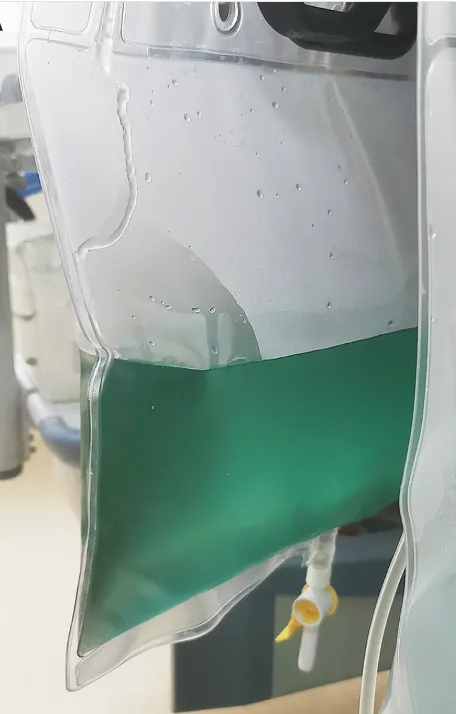

Confere esse caso de mudança de coloração no efluente do dialisato em um paciente em diálise contínua

Valkercyo Feitosa

3 anos atrás